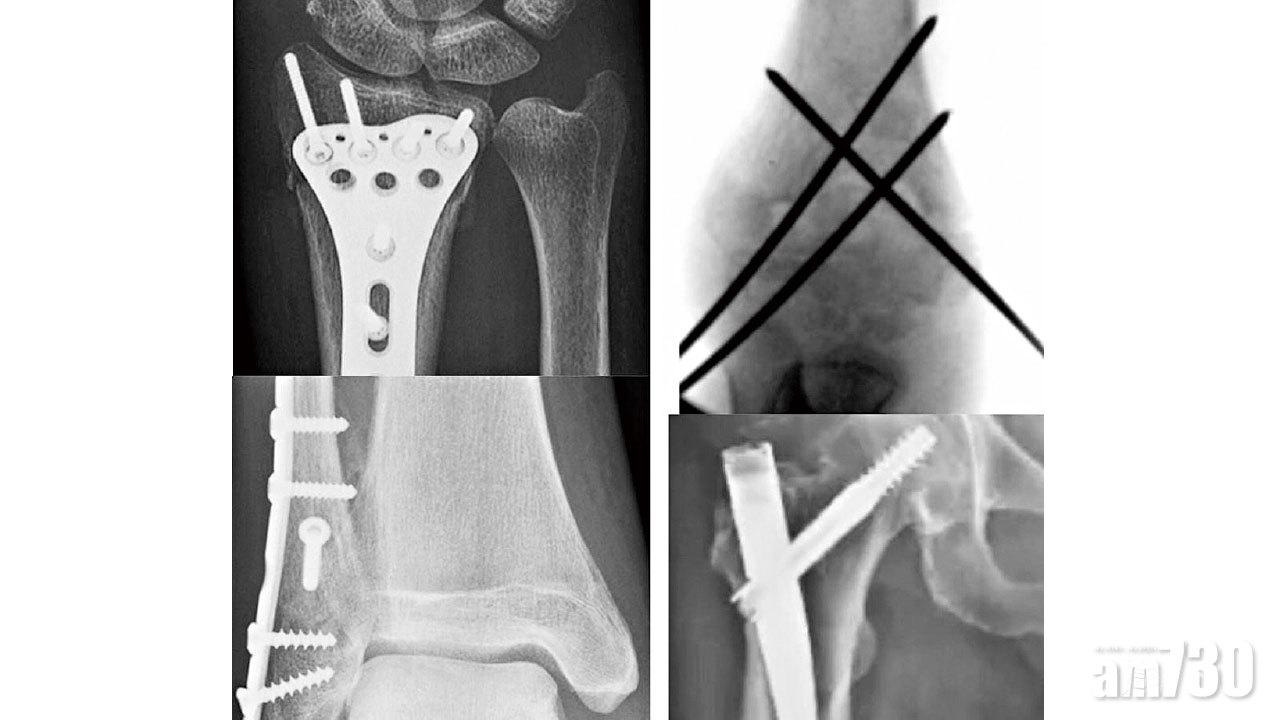

註釋:本文是黃偉文填詞、Dear Jane主唱的流行曲《銀河修理員》之二次創作。用於治療骨折的金屬植入物,主要由不銹鋼及鈦合金製成。常用的植入物包括:鋼針、螺絲、鋼片、髓內釘、鋼線和關節假體等。骨折手術可分為閉合式和開放式復位,以內固定術為主,並在特定情況下使用外固定支架或骨牽引。